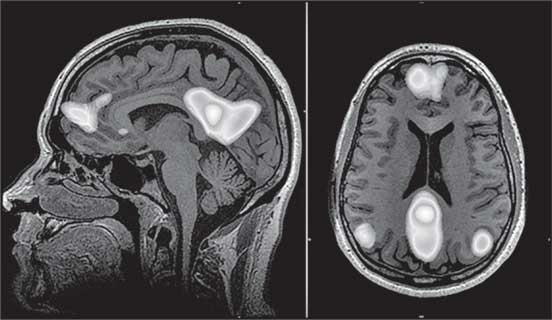

В 2001 году Маркус Райхл сформулировал концепцию дефолт-системы мозга (ДСМ). На первый взгляд может показаться, что это как бы «система ничегонеделания», но это не так. Выяснилось, что, когда мы отвлекаемся от дела, мы отвлекаемся на что-то внутри себя. Оказалось, что ДСМ – это сеть, которая отвечает за наши рассуждения о социальных отношениях. Оцените, как часто вы думаете о взаимоотношениях с друзьями или родственниками? На самом деле мы все постоянно на это отвлекаемся: доволь-на ли моя вторая половина, не обидел ли я коллегу, почему со мной не разговаривает ребенок и так далее.

Иллюстрация к книге — Мозг. Как он устроен и что с ним делать [i_040.jpg]

Рис. 40. Структуры дефолт-системы мозга (выделены светлым)

Вероятно, эта система, называемая также сетью пассивного режима работы мозга (СПРРМ), сформировалась в нашем далеком эволюционном прошлом, когда мы еще были стайными.